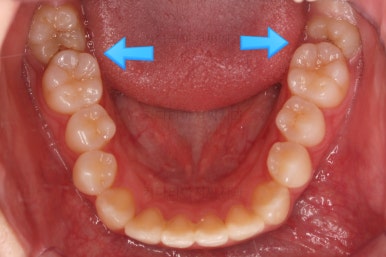

부산교정 키다리아저씨치과에 처음 내원하셨을 당시의 입안 모습과 X-ray 사진입니다.

맨 안쪽 치아가 마치 사랑니인 것처럼 누워있고 애매하게 나와있었어요.

문제는 해당 치아가 썩었다는건데, 기울어있는 치아를 제대로 치료할 방법은 사실상 없죠. 앞에 치아에 가려진 부분이 썩었으니깐요.

저대로 계속 놔두게 되면 누워있는 어금니 + 앞쪽 어금니 두 개 다 상해서 결국 뽑아야 되는 상황까지 벌어질 수 있어요. 그것도 양쪽으로 모두 다요.

초진 시 다른 부위들 사진입니다.

약간의 주걱턱 느낌에 약간의 돌출감, 전반적인 치열의 가지런한 느낌은 나쁘지 않았지만 약간의 불량한 교합상태였어요.